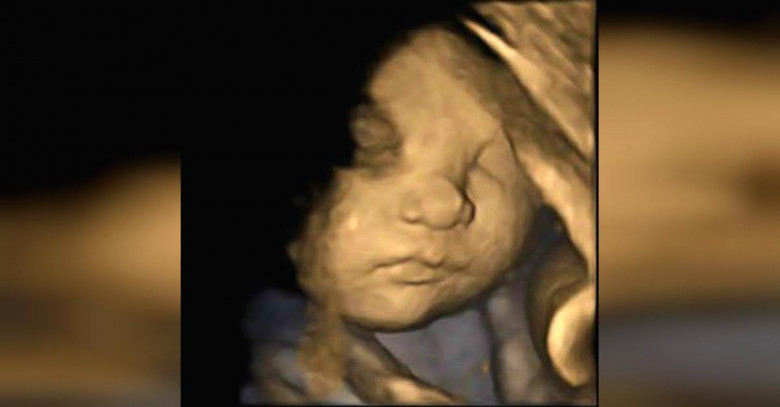

Результаты первого же УЗИ показали некоторые отклонения в развитии ребенка. А более серьезное обследование выявило, что у девочки синдром Дауна. Кроме того существовала большая вероятность других отклонений в развитии: ребенок мог родится слепым или глухим.

Суррогатная мать решила выносить девочку и оставить ее себе. На протяжении всего срока беременности Андреа находилась под наблюдением врачей, но несмотря на все меры предосторожности, здоровье девочки находилось под угрозой. В первые несколько часов после рождения маленькая Дэлани перенесла несколько операций!